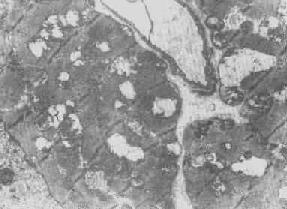

四、线粒体线粒体(mitochondrion)是细胞内主要的能量形成所在,故不论在生理上或病理上都具有十分重要的意义。 线粒体为线状、长杆状、卵圆形或圆形小体,外被双层界膜。外界膜平滑,内界膜则折成长短不等的嵴并附有基粒。内外界膜之间为线粒体的外室,与嵴内隙相连,内界膜内侧为内室(基质室)(图1-8)。在合成甾类激素的内分泌细胞(如肾上腺皮质细胞、卵甾滤泡细胞、睾丸的Leydig细胞等),线粒体嵴呈小管状。内外界膜的通透性不同,外界膜的通透性高,可容许多种物质通过,而内界膜则构成明显的通透屏障,使一些物质如蔗糖和NADH全然不能通过,而其他物质如Na+ 和Ca 2+等也只有借助于主动运输才能通过。线粒体的基质含有电子致密的无结构颗粒(基质颗粒),与二价阳离子如Ca2+及Mg2+具有高度亲和力。基质中进行着β氧化、氧化脱羧、枸橼酸循环以及尿素循环等过程。在线粒体的外界膜内含有单胺氧化酶以及糖和脂质代谢的各种转移酶;在内界膜上则为呼吸链和氧化磷酸化的酶类。 线粒体是对各种损伤最为敏感的细胞器之一。在细胞损伤时最常见的病理改变可概括为线粒体数量、大小和结构的改变: 1.数量的改变 线粒体的平均寿命约为10天。衰亡的线粒体可通过保留的线粒体直接分裂为二予以补充。在病理状态下,线粒体的增生实际上是对慢性非特异性细胞损伤的适应性反应或细胞功能升高的表现。例如心瓣膜病时的心肌线粒体、周围血液循环障碍伴间歇性跛行时的骨骼肌线粒体的呈增生现象。 线粒体数量减少则见于急性细胞损伤时线粒体崩解或自溶的情况下,持续约15分钟。慢性损伤时由于线粒体逐渐增生,故一般不见线粒体减少(甚至反而增多)。此外,线粒体的减少也是细胞未成熟和(或)去分化的表现。 2.大小改变 细胞损伤时最常见的改变为线粒体肿大。根据线粒体的受累部位可分为基质型肿胀和嵴型肿胀二种类型,而以前者为常见。基质型肿胀时线粒体变大变圆,基质变浅、嵴变短变少甚至消失(图1-9)。在极度肿胀时,线粒体可转化为小空泡状结构(图1-10,图1-11)。此型肿胀为细胞水肿的部分改变。光学显微镜下所谓的浊肿细胞中所见的细颗粒即肿大的线粒体。嵴型肿较少见,此时的肿胀局限于嵴内隙,使扁平的嵴变成烧瓶状乃至空泡状,而基质则更显得致密。嵴型肿胀一般为可复性,但当膜的损伤加重时,可经过混合型而过渡为基质型。 线粒体为对损伤极为敏感的细胞器,其肿胀可由多种损伤因子引起,其中最常见的为缺氧;此外,微生物毒素、各种毒物、射线以及渗透压改变等亦可引起。但轻度肿大有时可能为其功能升高的表现,较明显的肿胀则恒为细胞受损的表现。但只要损伤不过重、损伤因子的作用不过长,肿胀仍可恢复。 线粒体的增大有时是器官功能负荷增加引起的适应性肥大,此时线粒体的数量也常增多,例如见于器官肥大时。反之,器官萎缩时,线粒体则缩小、变少。

图1-11 线粒体肿胀(基质型)空泡变(心肌缺氧) 3.结构的改变 线粒体嵴是能量代谢的明显指征,但嵴的增多未必均伴有呼吸链酶的增加。嵴的膜和酶平行增多反映细胞的功能负荷加重,为一种适应状态的表现;反之,如嵴的膜和酶的增多不相平行,则是胞浆适应功能障碍的表现,此时细胞功能并不升高。 在急性细胞损伤时(大多为中毒或缺氧),线粒体的嵴被破坏;慢性亚致死性细胞损伤或营养缺乏时,线粒体的蛋白合成受障,以致线粒体几乎不再能形成新的嵴。 根据细胞损伤的种类和性质,可在线粒体基质或嵴内形成病理性包含物。这些包含物有的呈晶形或副晶形(可能由蛋白构成),如在线粒体性肌病或进行性肌营养不良时所见(图1-12);有的呈无定形的电子致